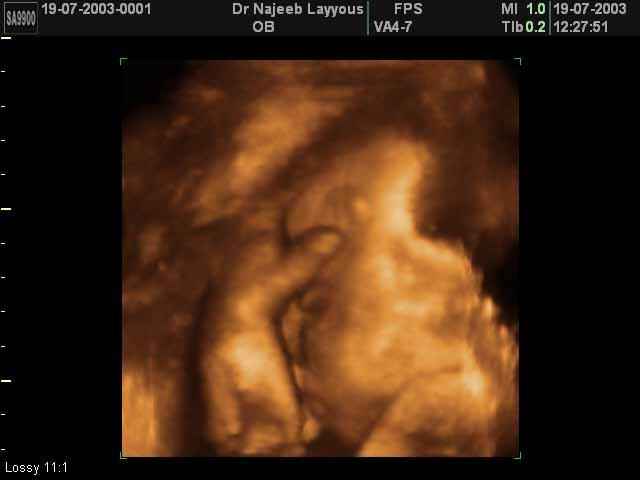

- صور جانبية لرأس الجنين

صور جانبية لرأس الجنين بجهاز الالتراساوند ثلاثي الأبعاد | الدكتور نجيب ليوس